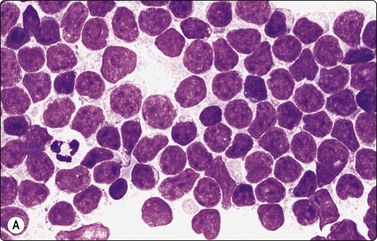

Fine needle biopsy samples of lymphoid tissue, nodal or extranodal, benign or malignant, as a rule have a very high cell content. This is obvious to the naked eye as the aspirate is smeared. It looks like a film of slimy material which turns gray on drying. The cytoplasm of lymphoid cells is fragile. Many cells are represented by naked nuclei or have only a small rim of cytoplasm. A variable number of rounded cytoplasmic fragments measuring up to 8 microns in diameter are scattered in the background (Fig. 5.1). The cytoplasmic fragments were named ‘lymphoglandular bodies’ by Söderström. The term ‘lymphoid globules’ is prefered since they are present in smears from any lymphoid infiltration, not only from lymph nodes. The fragments stain an uniform pale blue, identical to the cytoplasm of intact cells, with Giemsa stain. They differ from necrotic debris by their regular round shape and their uniform staining. Necrotic debris and nuclear fragments (karyorrhexis and apoptotic bodies) are characteristic of smears of small cell undifferentiated carcinoma (Fig. 5.2). The recognition of ‘lymphoid globules’ is of diagnostic value in the distinction of lymphoma from anaplastic carcinoma and some other tumors.

image

Fig. 5.1 Lymphoid globules

Numerous spherical fragments of blue cytoplasm of variable sizes dispersed between the lymphoid cells; some nuclear fragments. Large cell lymphoma of tonsil (MGG, HP).